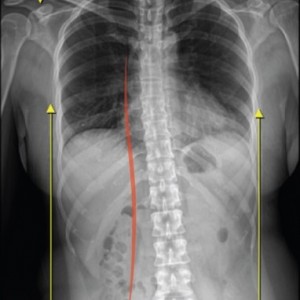

허리의 3대 질환

허리 디스크, 협착증, 척추전방전위증

허리 통증의 주요 가해자 허리디스크, 협착증, 척추전방전위증, 요추염좌, 디스크내장증, 압박골절, 척추분리증 등 이름은 다양하지만 따지고 보면 틀어진 자세로 인해

골반과 24개의 척추뼈가 중력을 버티는 과정에서 척추 하부에 있는

요추 3,4,5번에 압력이 집중된 결과일 뿐이고 그 결과물에 여러 가지 병명을 만들어 붙여 나온 질환일 뿐입니다.

따라서 실제 허리통증의 가해자는 허리디스크에 압력을 증가시킨 골반 틀어짐이나 다리길이 차이, 거북목, 틀어진 어깨, 측만증 등의 자세불균형입니다.

척추측만증 또는 좌, 우 한쪽으로 기울어진 척추로 인해 체중이 한쪽 허리로 집중된다면 장기적으로 체중이 기울어진 쪽 허리에 뼈가 자라거나 퇴행성 변화가 빠르게 진행됩니다.